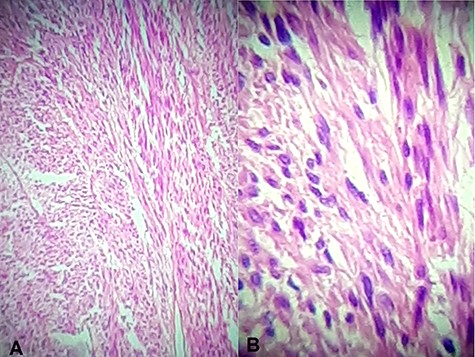

Histology showed a mixed cell type jejunal GIST with a mitotic index of <5/50 HPF—High Power Fields, clear resection margins and an intact tumour capsule (Figs 4 and 5).

Hematoxylin and eosin stain (A) Jejunal mass at ×4 magnification, (B) jejunal mass at ×40 magnification: consist of spindle cells of varying cellularity, hyperchromatic and nuclear pleomorphism with areas of epithelioid cells (mixed type GIST).